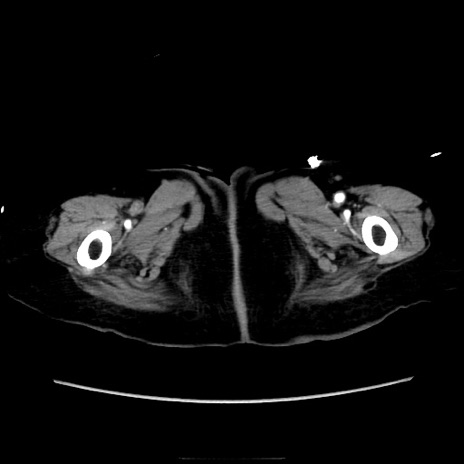

症例40(横断像)

【症例】90歳代女性

【主訴】腹痛・嘔吐

【現病歴】 食欲低下、嘔吐があり昨日他院受診。肺炎と診断され入院となる。入院後より腹部全体に圧痛あり。胃管留置され経過みていたが、症状持続するため、

当院転院となる。

【既往歴】胸椎圧迫骨折、胆石症

【身体所見】腹部:中央に激痛あり、圧痛あり、反跳痛不明

【データ】WBC 17100、CRP 18.82

横断像